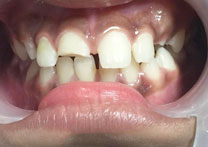

(4) Diastema Closure

Before Treatment

After Treatment

Patient with a complaint of a gap in between upper central incisors. Dental Veneers done to close the gap between the central incisors